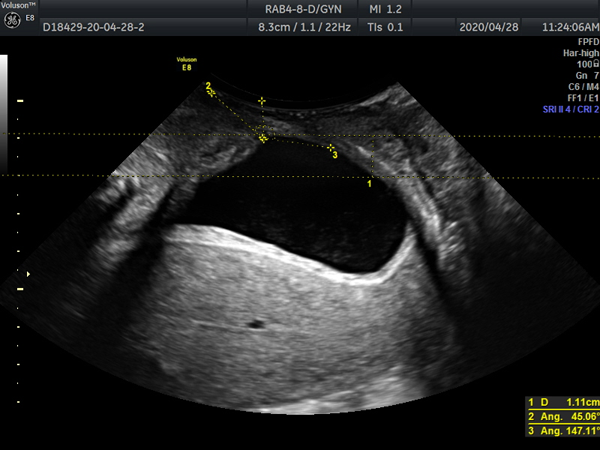

询问完病史,根据患者主述,值班大夫赵云初略判断患者可能是盆底功能障碍性疾病,建议患者行“盆底超声检查”,最终通过三维/四维超声确诊了患者的病症--GreenIII型膀胱膨出,盆底肌松弛引起的盆底功能障碍性疾病之一。这个病会引起尿潴留,导致反复泌尿系感染,病因找到了,患者被建议去我院妇科寻求帮助,下一步治疗方向有了,患者对我院工作人员连声道谢。

病因主要是妊娠、绝经后雌激素水平下降等引起盆底支撑结构损伤、松弛及功能障碍,目前在我国发病率较高。准确诊断的基础就在于对盆底结构及功能的准确认识,很多时候单纯的临床普通检查并不能获得盆底解剖以及功能改变的详细信息。 而盆底超声通过盆底组织的二维及三维/四维超声检查,获得盆底完整的声像图,可以比较直观的显示盆底各脏器的空间关系并明确诊断。

盆底超声不但可以直接观察盆底变化情况,而且膀胱移动度、尿道倾斜角、膀胱后角、尿道内口漏斗是否形成、子宫有无脱垂、直肠有无膨出、有无肠疝、肛门括约肌及肛提肌有无损伤等还可作为盆底情况客观影像学指标。